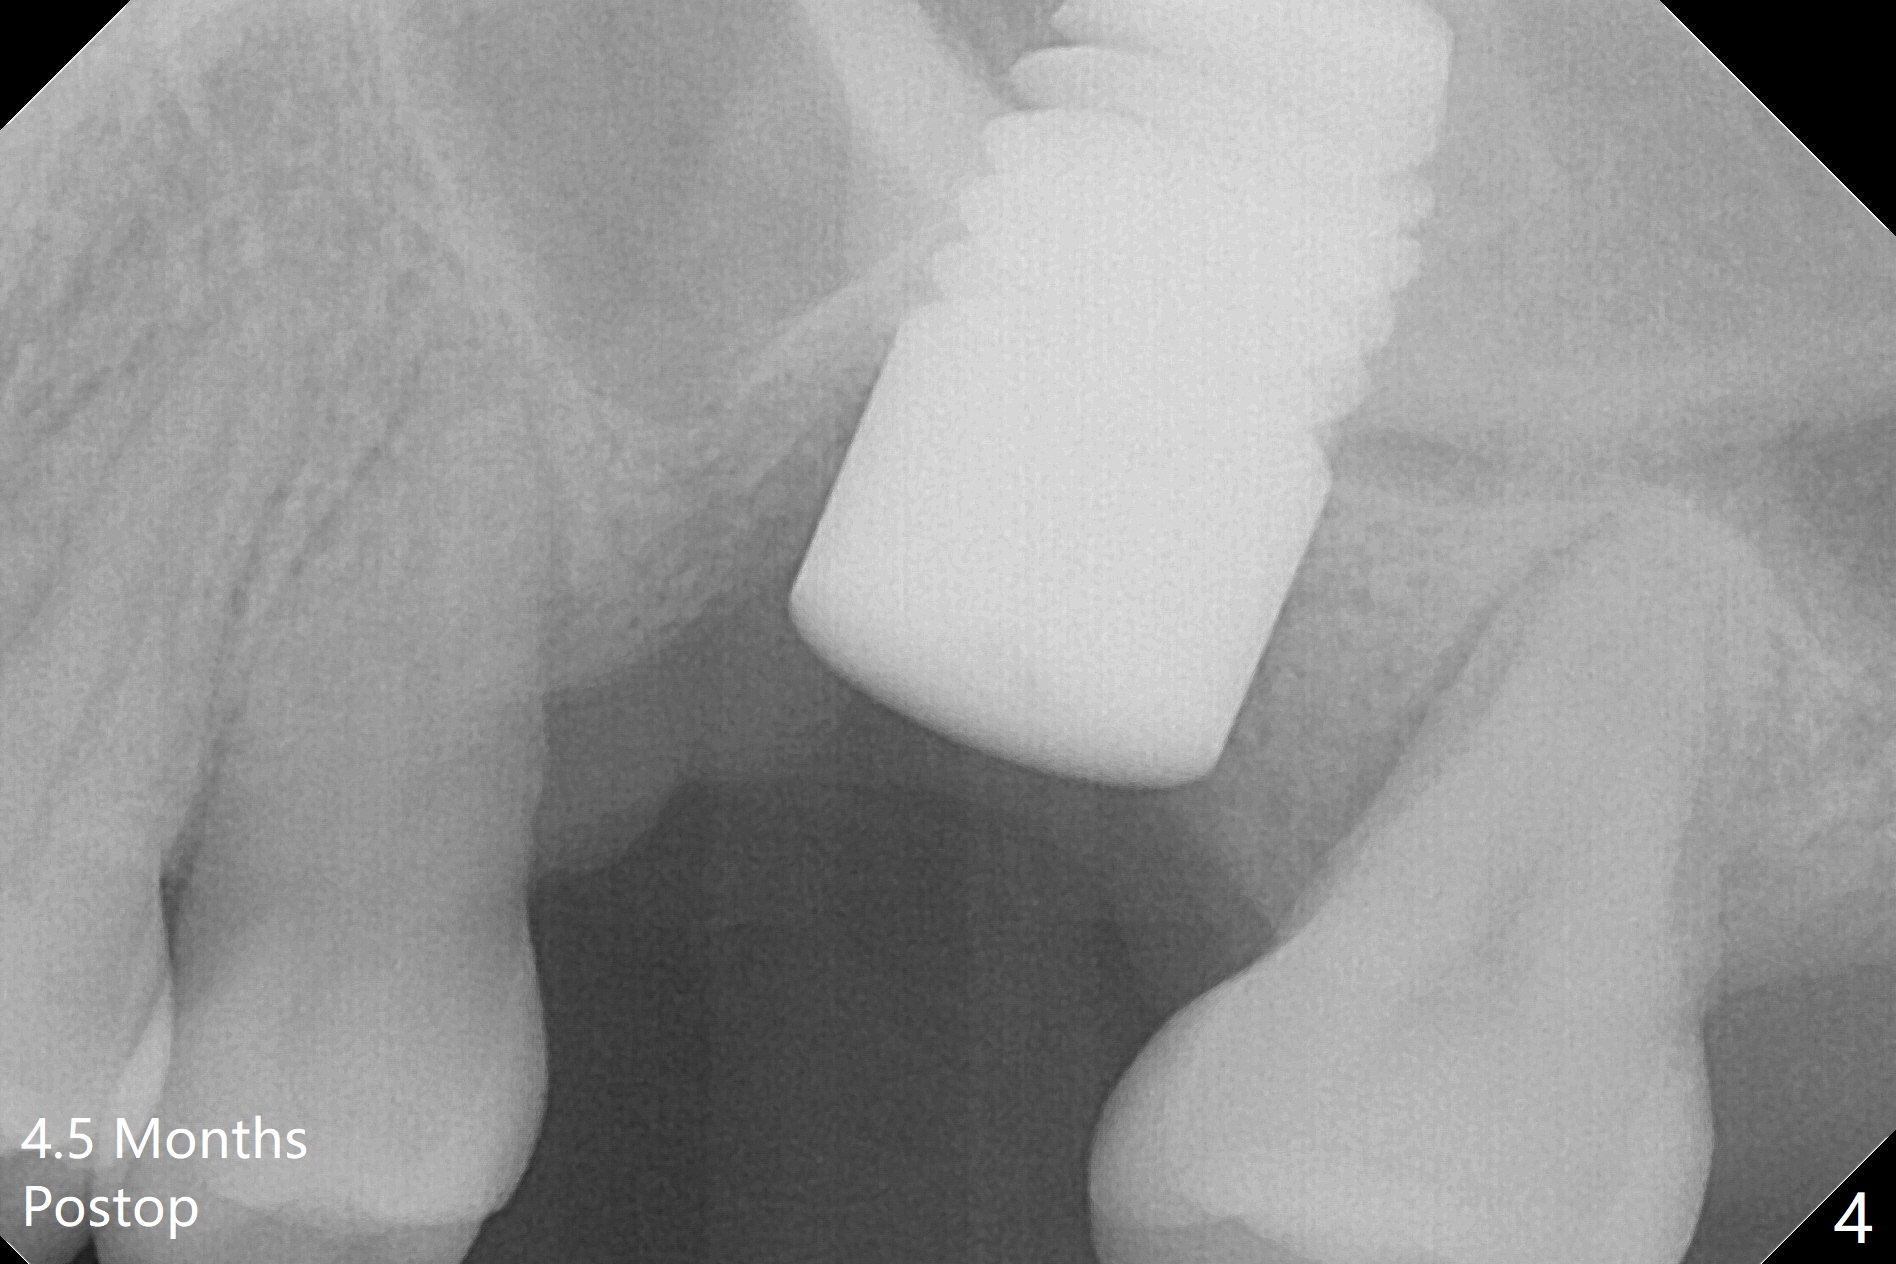

Three months post cementation, the implant at #14 is found loose (Fig.1: 6.5x11 mm) and removed. After removal of minimal granulation tissue, normal saline disappears into the apical end of osteotomy. In fact there is no bone apically, although the sinus membrane is intact. After try in of various taps (tapered and cylindrical, bone- and tissue-level), a 8x14 mm dummy implant is placed (Fig.2), followed by Osteogen plug and the same sized definitive implant, which has to be placed deeper to obtain ~ 45 Ncm (Fig.3). There is minimal thread engagement. If the implant fails, place 2 layers of PRF membrane apically, bone graft and 1 layer of PRF coronally for ridge preservation. A healing abutment will be placed to expose the coronal end of the implant ~ 4 months postop. The tissue-level implant remains subgingival 4.5 months postop (Fig.4). A 8 mm healing cuff cannot be placed even after laser gingivectomy. The implant is 2 mm subcrestal mesially. Torque wrench cannot reverse the implant at 60 Ncm. The implant is later reversed with Tatum wrench until it is turned with the torque wrench at 30 Ncm. The implant remains stable, while the healing cuff with Triple Antibiotic Ointment is placed. The healing cuff is stable 2 weeks later (Fig.5 C). With progressive loading for a month, a crown is cemented 9 months postop. There appears no bone loss 2.5 months post cementation (11 months postop, Fig.6). Return to Upper Molar Immediate Implant, Armaments, IBS #3 Xin Wei, DDS, PhD, MS 1st edition 04/30/2018, last revision 04/14/2019